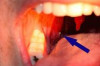

Tonsil stones (tonsillolith) are characterized by white to yellowish chunks in your throat. The cause of these foul- smelling, irregularly shaped stones is because of the sulfur-producing bacteria stuck on your mouth from food particles. Nasal drip can also be another cause for its formation. Anyone can get this and the symptoms can just make […]